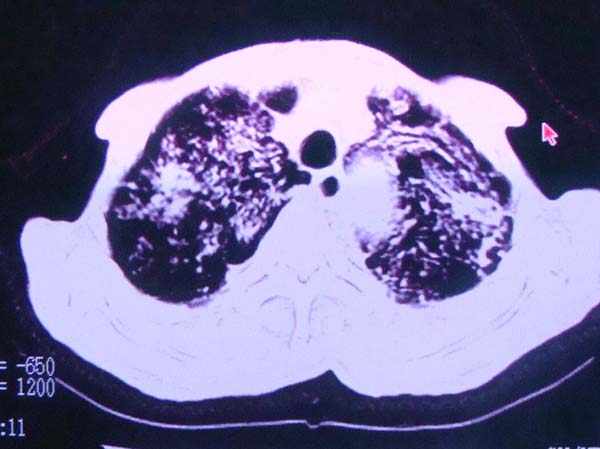

以下是引用zhangzhongshou在2008-2-15 22:25:00的发言:[br]片子照得不清,基本考虑1、细支气管肺泡癌2、亚急性血行播散型肺结核。请结合临床。片子细节显示不清,无法提供进一步意见。

以下是引用杀毒软件在2008-2-15 22:34:00的发言:[br]小叶中心性肺气肿。两肺弥漫性病变,肺泡微石病,过敏性肺炎,尘肺2期,特发性肺纤维化都有可能。[br]不象肺泡癌。